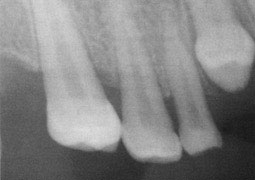

L'examen radiologique confirme le diagnostic de dysmorphie, et révèle une absence de plusieurs germes avec des formes radiculaires, sortant de la "normale".